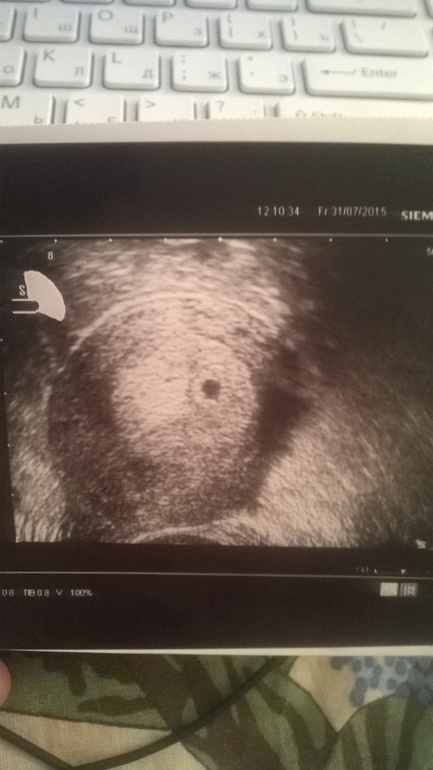

Девчонки, добрый день! Была сегодня на узи) Мою бусинку нашли!!!! По месячным сегодня 5,1 и по зачатию 2,6 (20 ДПО). По узи все тютелька в тютельку сошлось) Плодное яйцо 7 мм). Прилагаю фото сегодняшнего тестика и первое фото моей крошечки!